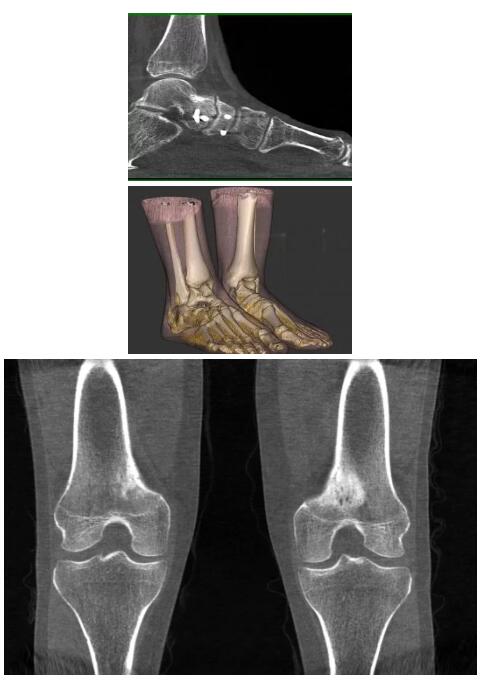

比如上面這款專用于足部和踝部掃查的CT成像系統(tǒng),患者在進行CT掃查時只需要站在上面即可,雙腳站或者單腳站都可以,當然,如果患者不是那么方便站著做完CT掃查,也可坐在上面。

這款CT掃查系統(tǒng)自帶屏蔽裝置,它的體積非常小,僅需要極小的空間即可,并不像常規(guī)CT那樣需要一間單獨的檢查室。此外,這種CT掃查的速度非常快,僅需30秒左右可以完成檢查,輻射劑量相對常規(guī)的CT要少許多,尤其適合醫(yī)院的骨科使用。

而患者站著做足部或者踝部做CT檢查還有個好處是,可以檢查患者在負重的情況下,骨關節(jié)的真實情況,而躺著做CT掃查時未必能看出來。負重CT掃查特別是對于受傷的運動員或者舞蹈員來說意義更大,能夠更準確地評估傷情,幫助他們盡早復原。

以下是這些“特立獨行”的CT所拍出來的圖像: